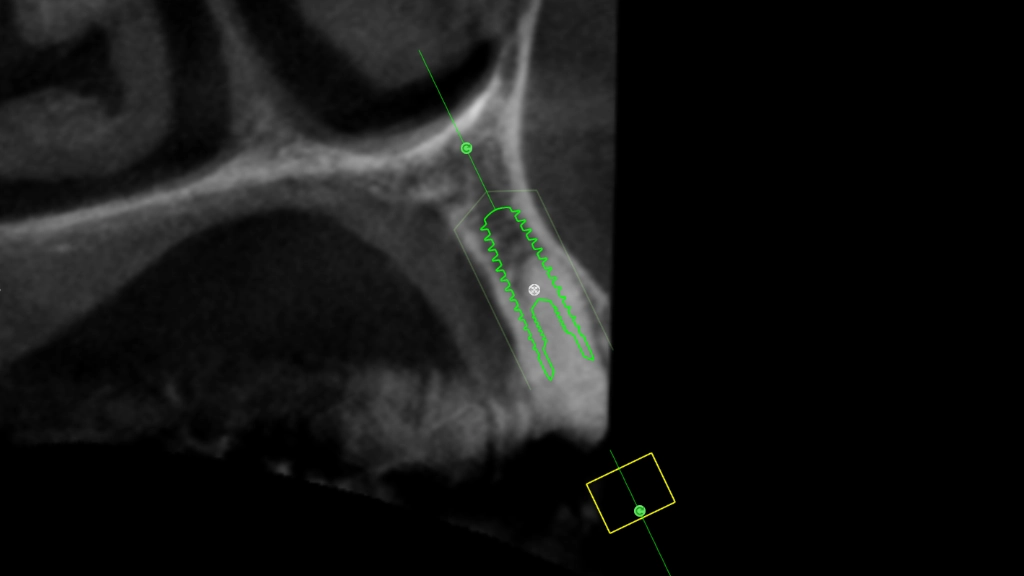

We maken een CT scan van je gebit, een gebitsscan met een soort cameraatje en dan gaat Hurx aan de slag: buiten de mond. In een simulatieprogramma maken we een waxup model, een fictieve planning implantaat en als alles meezit een guide. Een waxup model is een inschatting hoe de nieuwe tand eruit moet komen te zien, we kunnen de implantaatpositie daarop aanpassen.

De röntgenbeelden worden met dit model en de waxup samengevoegd: de positie, implantaatlengte en -breedte worden bepaald:

Daarna wordt een zogenaamde guide ontworpen. Dit is een malletje die tijdens het implanteren exact passend over het gebit geschoven wordt, net als een beugel. In dat malletje is de exacte richting en diepte bepaald. Wij beschikken over een professionele, nauwkeurige 3D printer: het ontwerp wordt werkelijkheid.